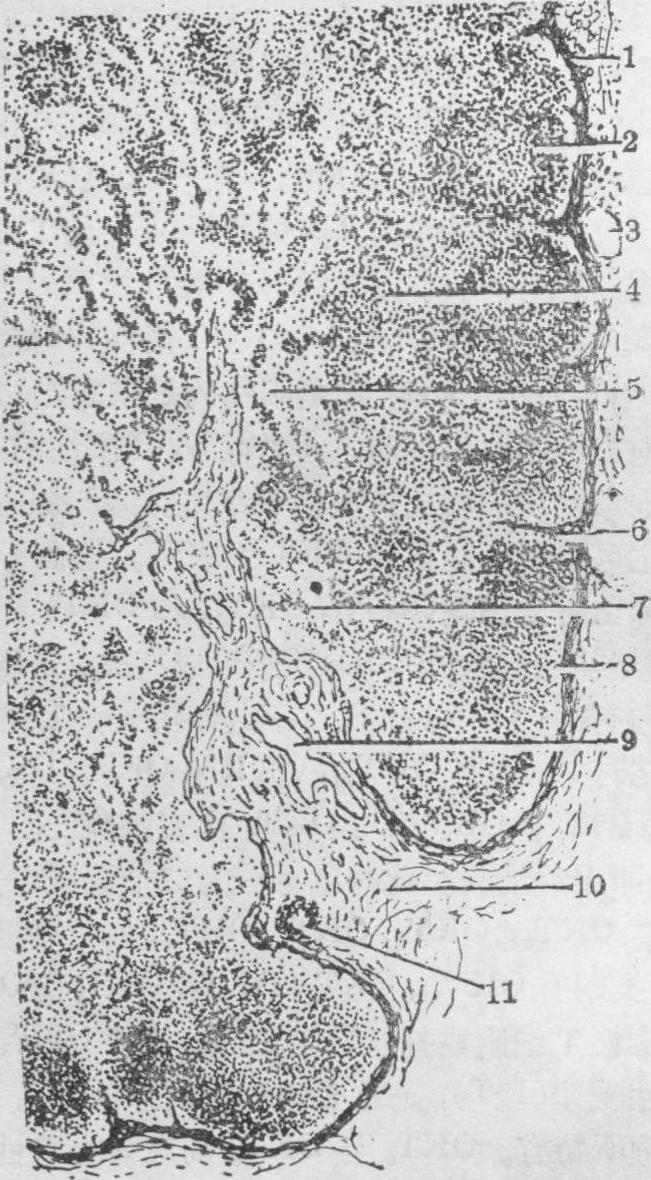

成群散于淋巴回流通路上的次级淋巴器官。其大小不等,形状不一。通常呈豆形,其凹陷处称为门部,是血管、神经和输出淋巴管进出的通道,输入淋巴管则从淋巴结表面不同部位进入(图1)。

图 1 淋巴结结构及其血液、淋巴通路示意图

1. 胸腺依赖区; 2. 生发中心; 3. 被膜下窦; 4. 皮窦;5. 小梁; 6. 皮质毛细血管网; 7. 被膜;8. 输入淋巴管;9. 小结毛细血管网; 10. 毛细血管后微静脉;11. 髓质毛细血管网; 12. 髓窦; 13. 髓索;14. 输出淋巴管;15. 小动脉; 16. 小静脉